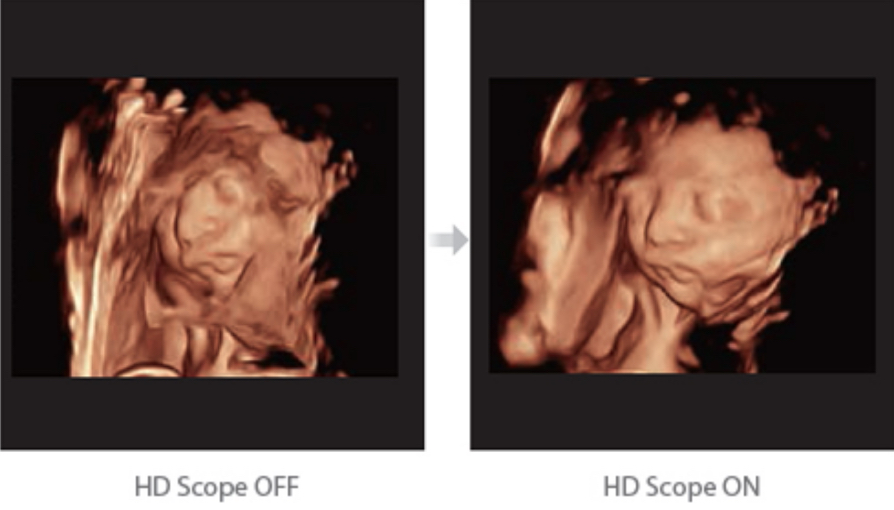

Acquiring an optimal view of the fetal face in 3DUS is cumbersome and time-consuming. In some cases, it is impossible to get rid of the occlusions such as cord, placenta, uterus, and extremities. The new Resona 6 with Zone Intelligence provides a fast and intelligent optimization for fetal face with simple one-touch operation. It can immediately remove occlusions in the volume data and eliminate unwanted noise information, and generate an optimal view of the fetal face with minimized effort.